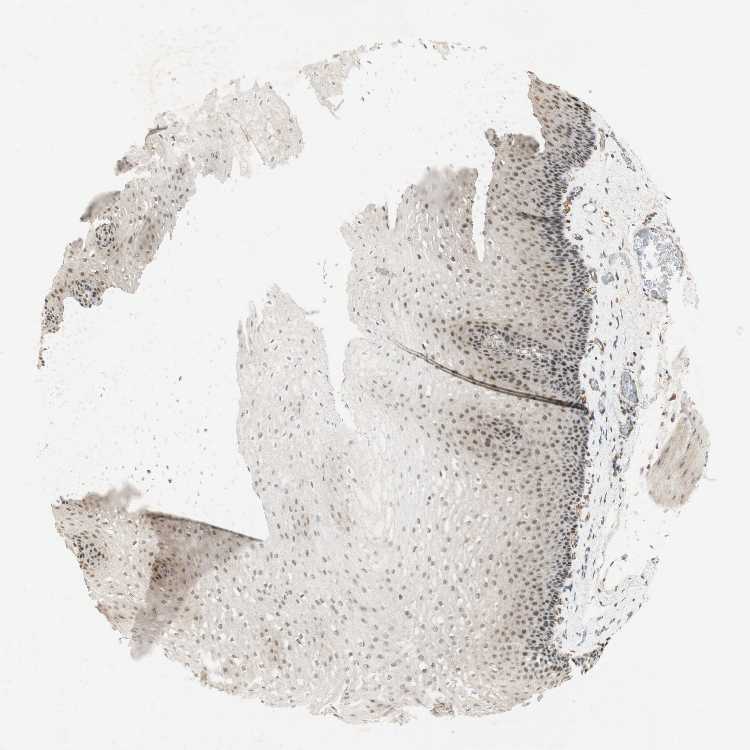

ESOPHAGUS - Antibody stainingi

Antibody staining in the annotated cell types in the current human tissue is reported as not detected, low, medium, or high, based on conventional immunohistochemistry profiling in selected tissues. This score is based on the combination of the staining intensity and fraction of stained cells.

Each image is clickable and will lead to virtual microscopy that enables deeper exploration of all samples and also displays staining intensity scores, fraction scores and subcellular localization as well as patient and tissue information for each sample.

Antibody HPA063131Antibody CAB011662

Squamous epithelial cells LowHigh